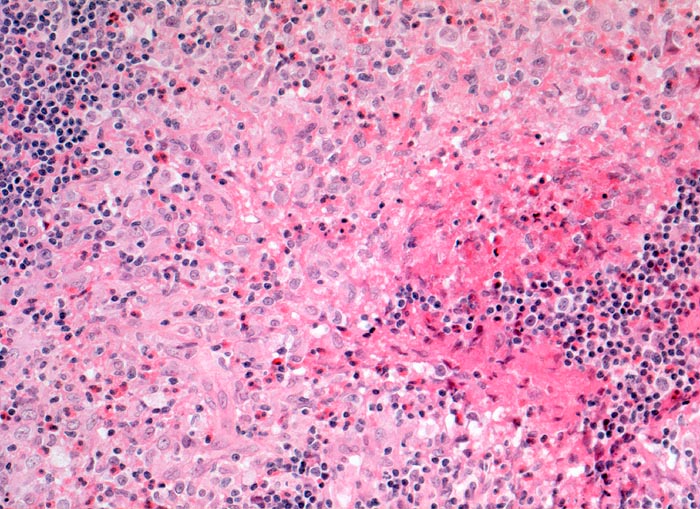

Infiltratherd bestehend aus Langerhanszellen mit bohneförmigen Kernen und reichlich hellem Zytoplasma. Dazwischen zahlreiche eosinophile Granulozyten.

CD1a und S-100 positive Langerhanszellen in den hellen Infiltratherden